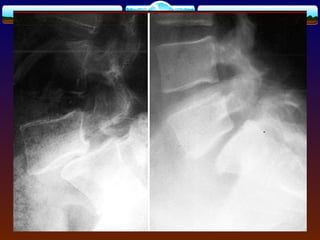

Imaging Studies  lumbarAP, lateral, and oblique views.  lateral flexion and extension,MRI  Meyerding’s system for grading: Grade 1 is 25%, Grade 2 is 50%, Grade 3 is 75%, Grade 4 is 100% displacement , GradeV --spondyloptosis